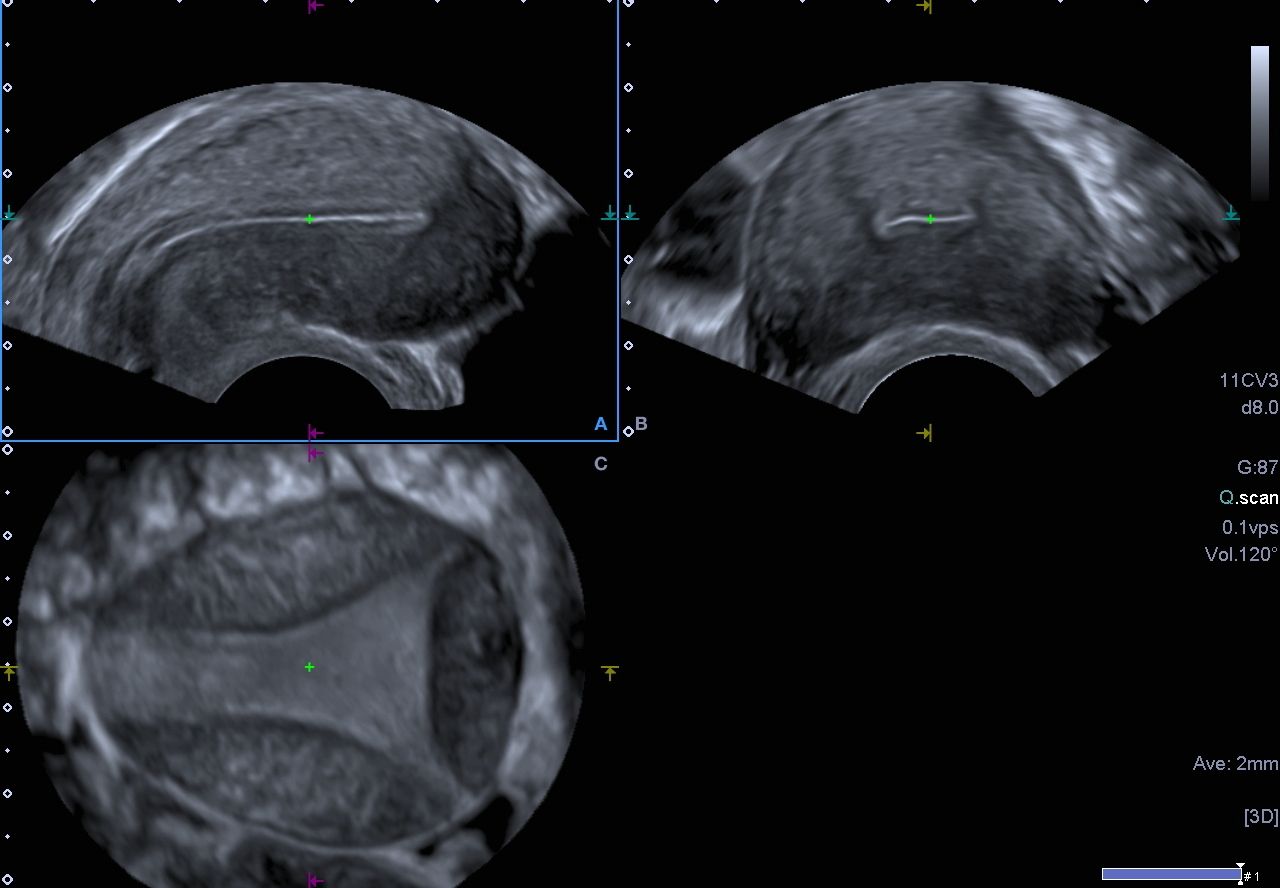

Individuelle Anpassung mit 3D-Ultraschall

Um die passende Spirale für jede Frau zu finden, vermessen wir die Gebärmutter präzise mittels 3D-Ultraschall. So garantieren wir optimale Sicherheit und Komfort.